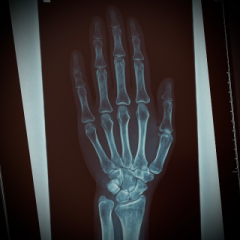

レントゲン写真。。

ぁ、

骨、

カッコぃぃ。。♡

我ながら、

イイ骨だゎ。。(笑)

骨に、

異常はなぃらしぃ。。

ヨカッタ。。